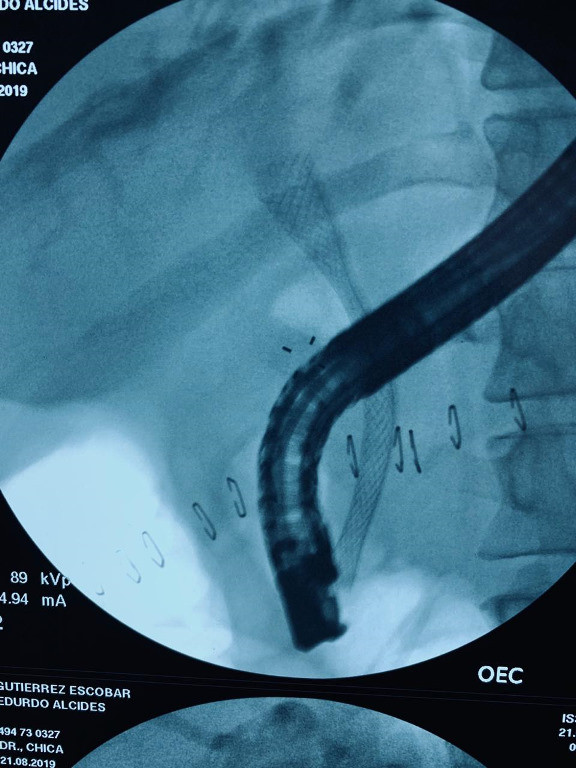

Cálculo gigante por coledocoliatisis